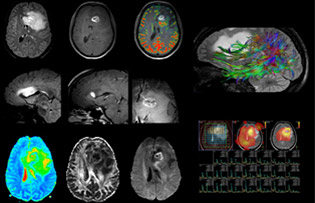

Dr. Savatovsky uses five or six different ExamCards for imaging a mass or a known tumor in the brain. “If there is a mass in the brain we try to characterize it to inform the neurologist for determining next steps or to help neurosurgeon prepare for a surgery or biopsy. For follow-up after treatment we have different protocols for different treatments and we adapt for intra- or extra-axial tumors.” “That is the most comprehensive exam we would do. Ingenia has the good spatial resolution and high SNR to provide all this information, and the flexibility to use shorter sequences, so we can do a very comprehensive examination in a limited time.”

“The biggest challenges are properly characterizing the lesion and giving the surgeon all the information needed, such as the location of vessels and functional areas. Sometimes a very comprehensive exam is necessary, such as when a mass has been discovered at another hospital after which the patient is referred to us. We then do both lesion characterization and preoperative imaging in one exam, so both morphologic and functional assessment. For morphologic assessment we will use pre- and post-contrast T1-weighted imaging, FLAIR to assess infiltration, and diffusion. For functional characterization we will perform perfusion, spectroscopy, and susceptibility weighted imaging to look for micro vessels or micro hemorrhage inside the lesion[4]. For preoperative imaging we perform specific morphologic imaging that is compatible with the navigation system; depending on the location of the tumor, we would do fMRI or DTI.”